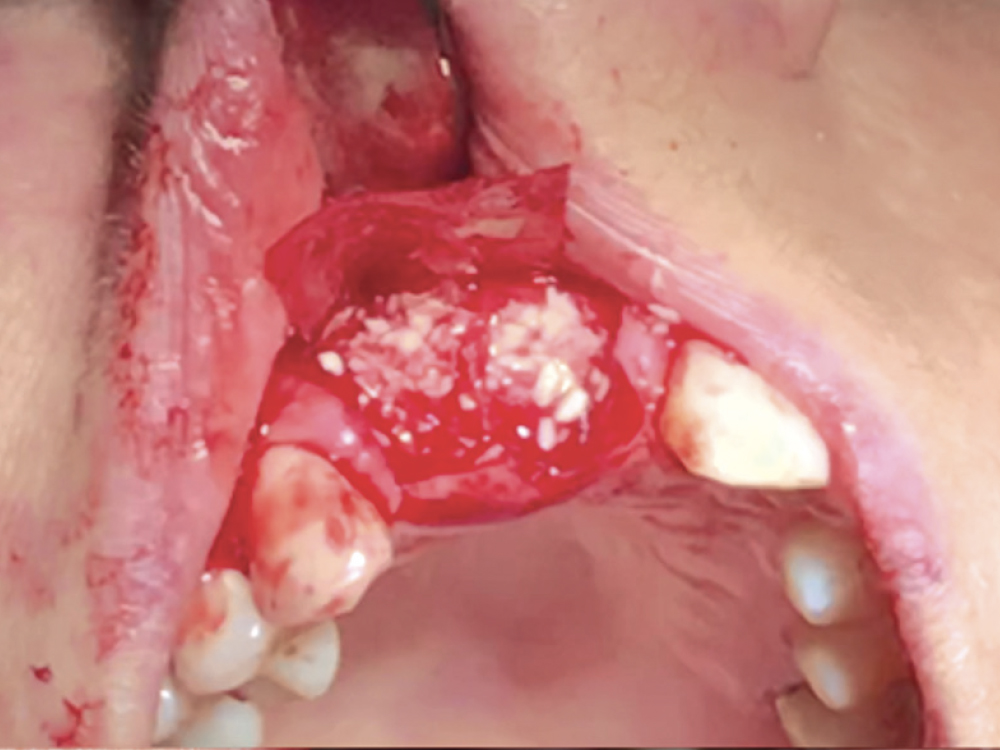

Bony Defect Evaluation A

Bony Defect Evaluation C

Bony defect evaluation: (a) Flap reflection allows the clinician to visually evaluate the size and location of the fenestration to determine whether the defect will compromise implant positioning or primary stability when immediate implant placement is desired; (b) Examples of a large fenestration (green arrow) and loss of the buccal plate (blue arrow), either of which would contraindicate immediate implant placement due to the inability to obtain primary stability; (c) Additional example of flap reflection to show the fenestration.